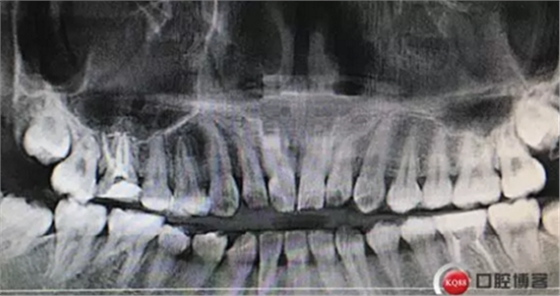

專科檢查:頜面部對稱,左側(cè)顳下頜關(guān)節(jié)張口末閉口初清脆彈響,唇舌無麻木,口腔衛(wèi)生良好,可見散在少量結(jié)石,無明顯口腔異味。

牙列完整,后牙中性關(guān)系,前牙開合,中線對齊。16合面大面積齲壞,內(nèi)褐色腐質(zhì),冷診無反應(yīng),叩痛(+-)。36合面樹脂充填,充填物在位,頰側(cè)冠折,折線位于齦緣下,冷診無反應(yīng),叩痛(+)。其他無殊。

診斷:36冠根折。